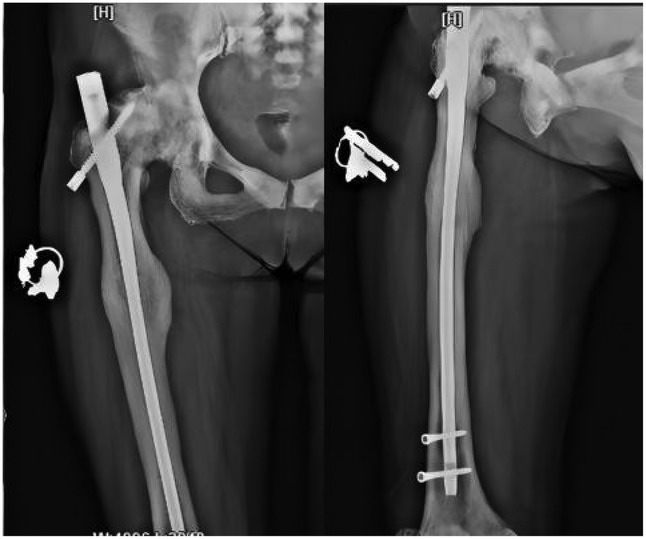

Following admission, the patient received symptomatic treatment including anti-inflammatory and analgesic therapy. Relevant laboratory tests and routine preoperative examinations revealed no significant contraindications for surgery. It was planned to perform a procedure to remove the internal fixation device from the right femoral trochanteric fracture and a closed reduction with intramedullary nail internal fixation for the right femoral fracture. The patient was placed in a supine position on a traction bed. An incision was made along the original surgical scar at the right hip, and the internal fixation device was removed. The apex of the right greater trochanter was then exposed. The needle insertion point was located at the anterior-medial one-third of the greater trochanter apex, slightly medial. The position of the guide wire was verified under fluoroscopy. The fracture was reduced on the traction bed, and the proximal end was dilated to 13 mm. and the distal end was dilated to 11 mm. After confirming the measurements, a 10 mm × 360 mm femoral intramedullary nail was placed. Under fluoroscopy, the fracture reduction was satisfactory. Two distal screws were locked in place using a targeting device, and the fracture ends were tapped and compressed. One proximal locking screw was inserted, and a 0 mm tail cap was installed. The surgery lasted 3.0 h, with an intraoperative blood loss of approximately 260 mL. On the second day postoperatively, a cephalometric and lateral x-ray examination of the femur was performed, with no abnormalities detected (Figure 2). The patient was discharged five days later, and was instructed to take anti-osteoporosis treatment after discharge, and isometric contraction of quadriceps femoris and ankle pump exercise were performed in bed 1–2 weeks after operation. 2–6 weeks after operation, straight leg lifting training, hip joint mobility training and partial weight-bearing exercise with walker were carried out; Six weeks after the operation, the patient changed to walking with one leg to carry out daily life training. One year after the operation, the x-ray examination showed that the fracture of femoral cadres healed well (Figure 3). During a follow-up period of over three years, the patient exhibited no significant neurological or motor dysfunction and no other complications were observed. The quality of life of patients has been greatly improved.

Figure 3. Follow-up x-rays taken one year after surgery showed good fracture healing and no abnormalities in the internal fixation device.